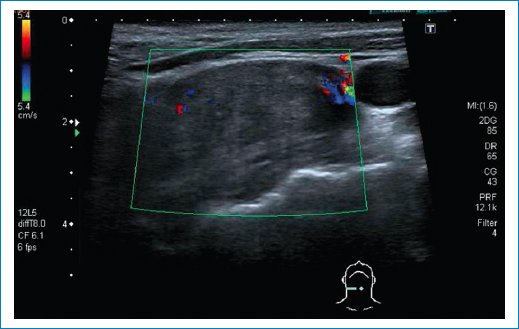

Se trata de un varón de 57 años, fumador, cuyo médico de familia aprecia a inicios de agosto de 2023 adenopatías cervicales derechas en aumento de varios meses de evolución, de consistencia media, no adheridas a planos profundos e indoloras. Es valorado por otorrinolaringología (ORL) con nasofibrolaringoscopia, en la que se aprecia abombamiento de la rinofaringe derecha, y se solicita ecografía cervical que identifica una masa sólida situada a la altura y por encima de la bifurcación carotídea, enfocándose como un paraganglioma (Fig. 1). Al ver los resultados, por parte de ORL se solicita TC.

Figura 1. Imagen tomada en plano horizontal por encima de la bifurcación carotídea mediante ecografía con modo Doppler color. Se aprecia una lesión ligeramente hipoecoica, relativamente homogénea, con vascularización periférica.